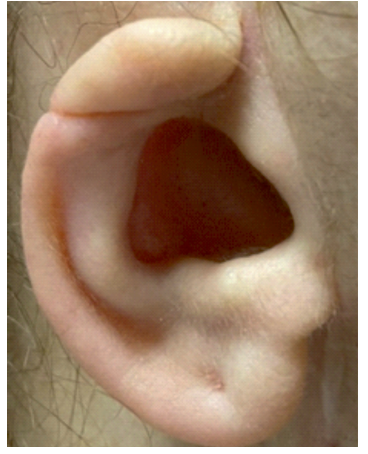

Doente de 62 anos, sexo feminino, leucodérmica, com antecedentes pessoais de dislipidemia, osteoporose e hipotiroidismo, apresentou-se em consulta de consulta de Otorrinolaringologia (ORL) do Hospital Pedro Hispano (HPH) por um quadro de hipoacusia do ouvido direito desde nascença e hipoacusia do ouvido esquerdo desde há 2 anos, associado a acufeno, constante, tipo água do mar. Sem outras queixas da área ORL. Tinha como antecedentes cirúrgicos, cirurgia reconstrutiva do pavilhão auricular direito em 2010 em contexto particular, para a qual não apresentava registos cirúrgicos. Sem história de reabilitação auditiva. O exame geral ORL revelava um pavilhão auricular esquerdo normalmente implantado, sem malformação, com CAE permeável e membrana timpânica sem alterações. O pavilhão auricular direito apresenta uma microtia grau II (figura 1, tabela 1), com meato acústico externo presente, canal auditivo externo em fundo de saco, não sendo visualizada a membrana timpânica. À acumetria, apresentava uma prova de Rinne negativa à direita, positiva à esquerda, com o teste de Weber a lateralizar para a direita.

A doente foi diagnosticada com uma microtia grau II (tabela 1) e atrésia congénita do CAE do tipo B (tabela 2 e figura 1 ) do ouvido direito que condicionava uma surdez mista severa.

O sistema de estadiamento clínico de Marx é uma ferramenta utilizada para classificar a microtia em quatro estadios, com base na severidade da malformação2) (tabela 1). No nosso caso a doente apresenta um grau II, em que algumas caraterísticas de um pavilhão auricular normal são reconhecíveis, neste caso o tragus, antitragus, lóbulo, concha auricular e meato auditivo externo.

O sistema de estadiamento clínico de Weerda é uma ferramenta utilizada para classificar a atrésia congénita do canal auditivo em três estadios, com base na gravidade da obstrução do canal auditivo3 (tabela 2 e figura 1). No nosso caso a doente apresentava um tipo B, com patência parcial do CAE lateral, porém com uma placa medial atrésica.